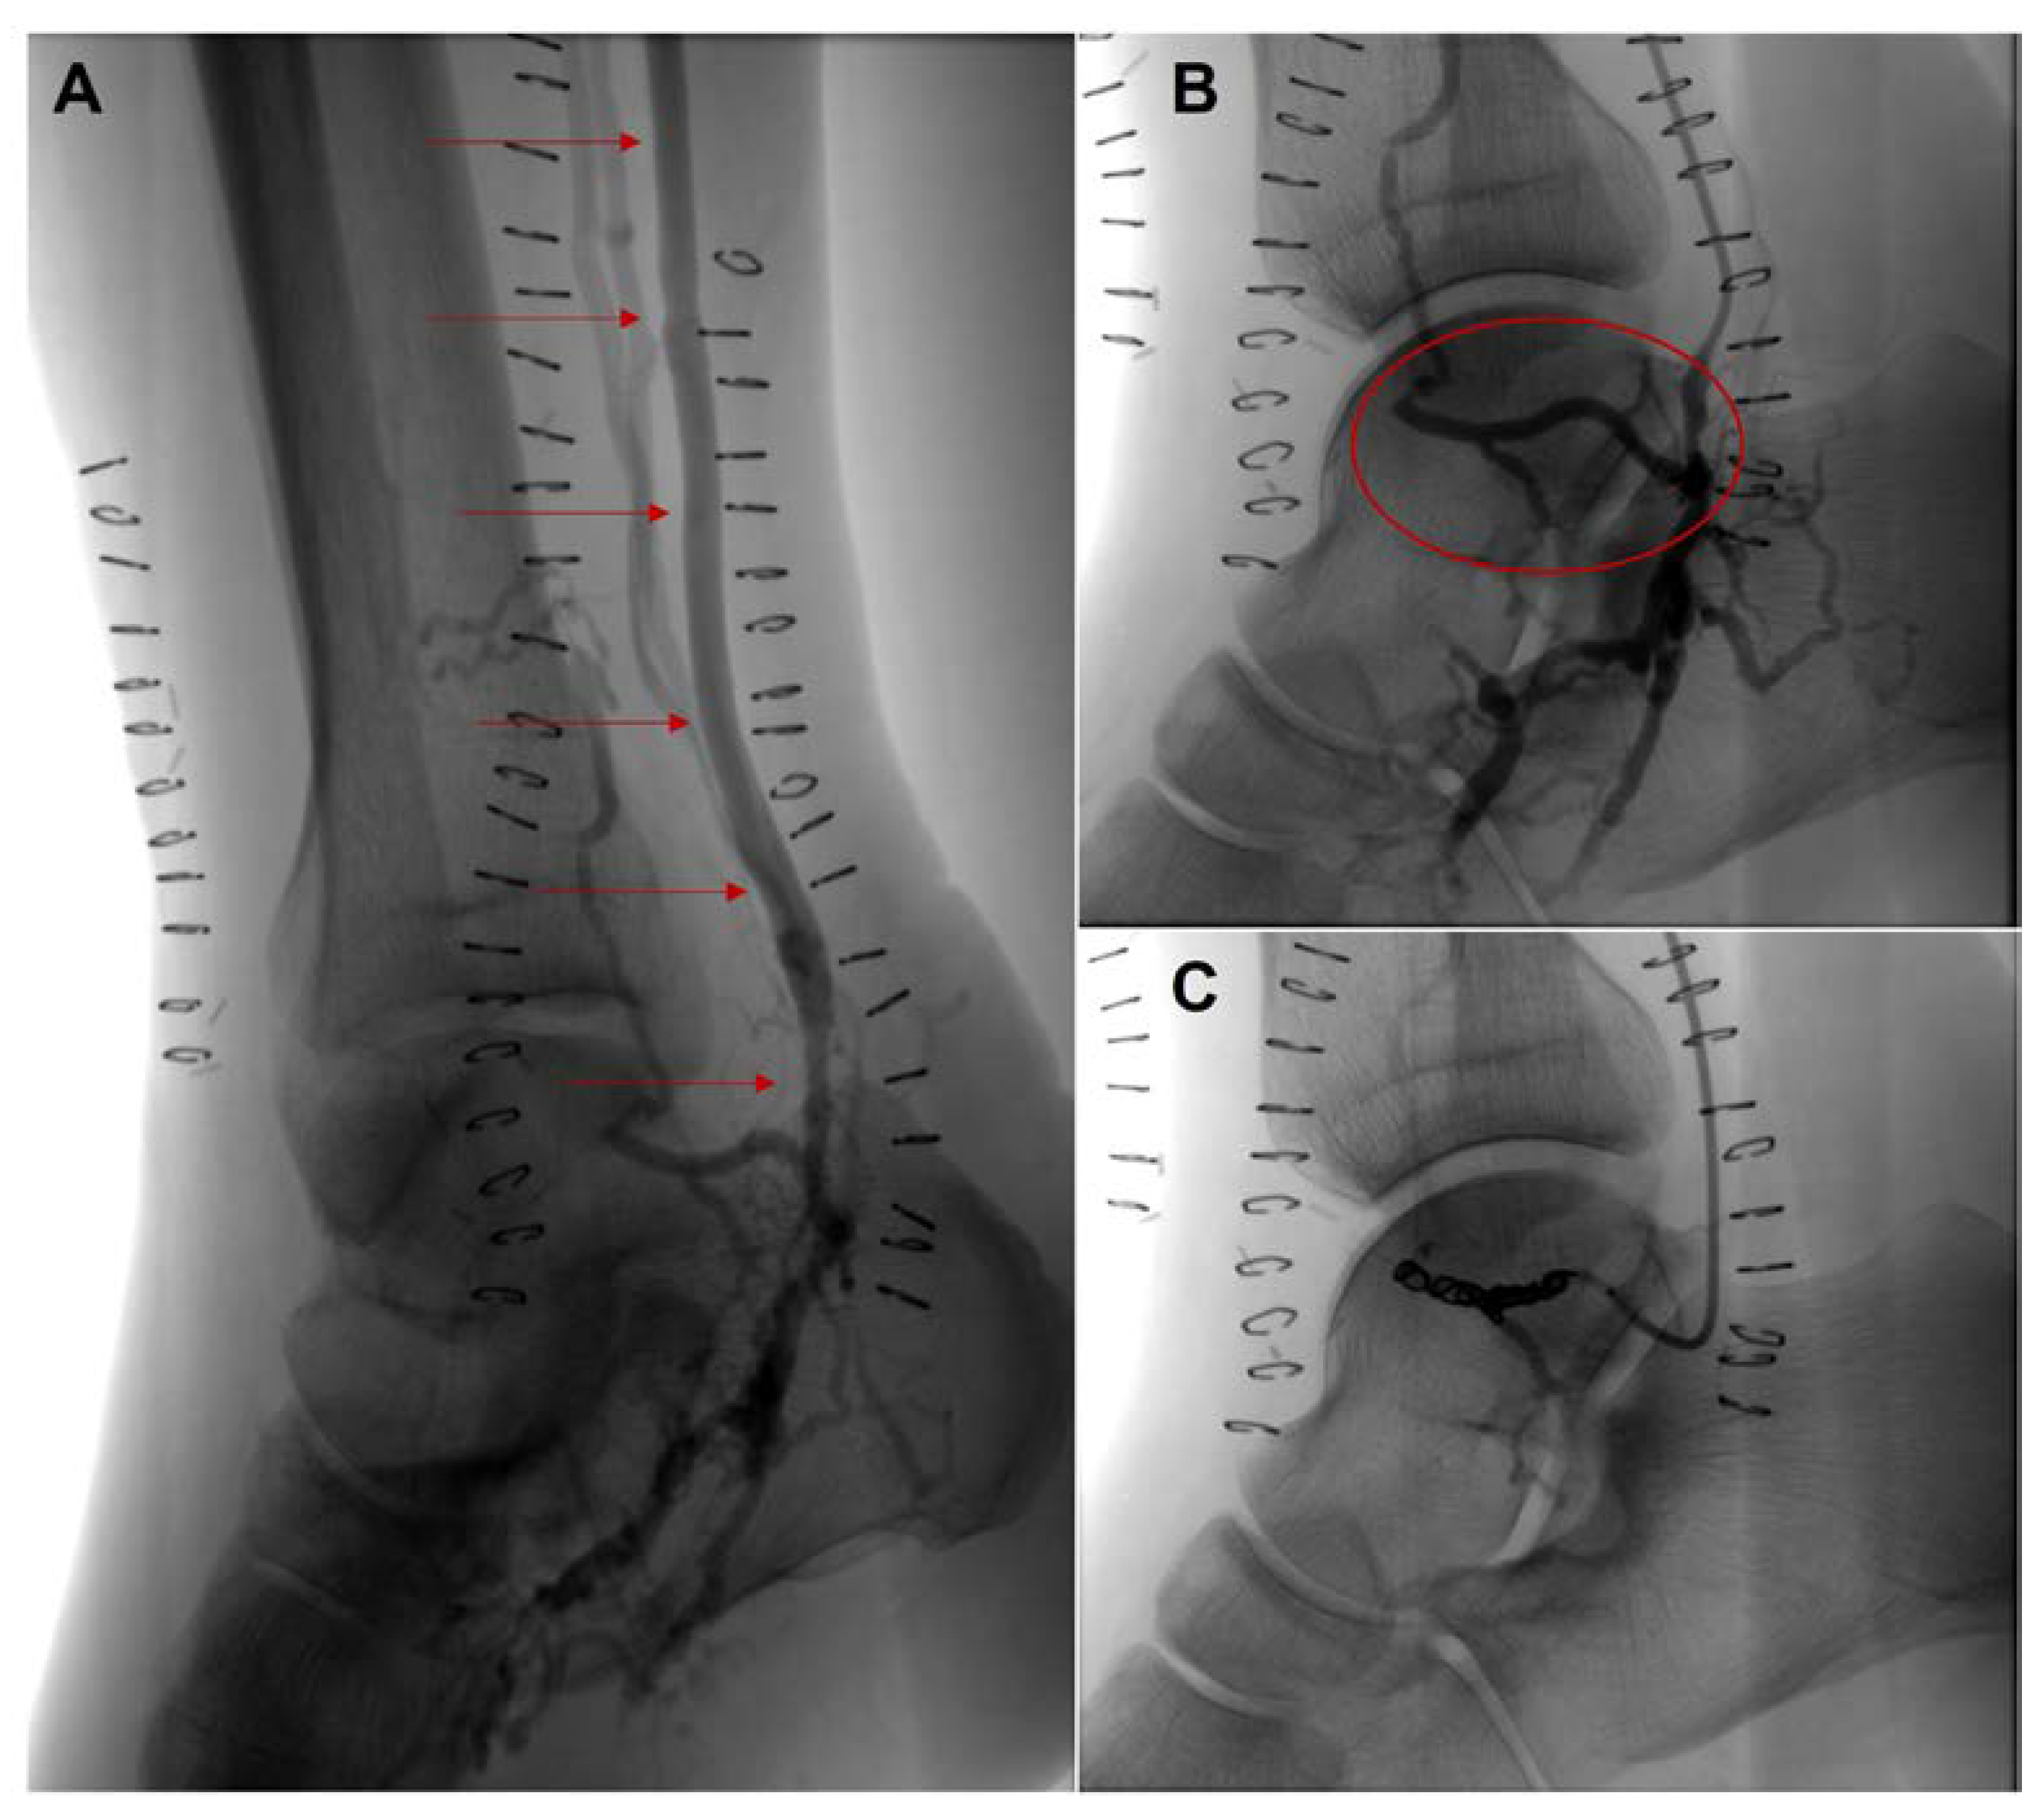

Conversion of Femoral-Tibial Bypass Surgery into Deep Vein Arterialization in a Patient with Severe Peripheral Artery Disease: Post-Operative Computed Tomography and Angiography Findings

2. Case Description

Parillo, M.; De Stefano, D.; Catanese, V.; Mallio, C.A.; Spinelli, F.; Stilo, F.; Quattrocchi, C.C. Conversion of Femoral-Tibial Bypass Surgery into Deep Vein Arterialization in a Patient with Severe Peripheral Artery Disease: Post-Operative Computed Tomography and Angiography Findings. Hearts 2023, 4, 12-19. https://doi.org/10.3390/hearts4010002